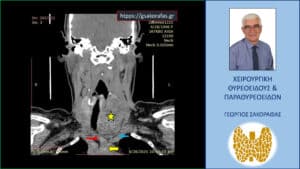

Αξονική τομογραφία -διατομή σε κατά μέτωπο επίπεδο. Ο ευμεγέθης όζος (κίτρινος αστερίσκος) εκτείνεται μεταξύ της έκφυσης της αριστερής κοινής καρωτίδας (μπλε βέλος) και του βραχιονοκεφαλικού στελέχους (κόκκινο βέλος), φθάνοντας σε βάθος στις παρυφές του αορτικού τόξου (κίτρινο βέλος).